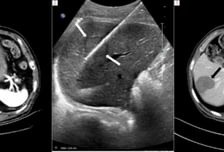

"열·전기로 암세포 파괴" 매년 3000여건 시행…재발·전이암에 큰 효과

암 치료의 지평이 넓어졌다. CT나 초음파 영상을 보며 전극(냉각)침· 안테나를 종양에 찌른 뒤 에너지를 주입해 암세포를 없애는 '국소 암 절제술'이 수술, 항암, 방사선 치료와 시너지 효과를 내며 암 환자의 새로운 치료 선택지로 부상하고 있다. 국소 암 절제술은 현재 간암, 신장암, 폐암에 국한해 적용 대상이 제한적이긴 하지만 수술에 버금가는 효과를 보이는 것으로 보고된다. 특히 간암(원발성 혹은 대장암으로부터 전이, 3cm 이내, 3개 이내)은 수술과 거의 대등한 치료 성적을 보인다. 신장암 역시 로봇·복강경 수술과 비교해 치료성적은 비슷하면서도 환자 부담이 적어 의료진의 환영을 받는다. 임상 현장에서는 열, 냉각, 전기 등 다양한 종류의 에너지원이 암세포를 죽이거나 사멸시키는 데 이용되고 있다. 고주파 절제술(Radiofrequency ablation)와 극초단파 절제술 (Microwave ablation)는 열에너지를, 냉동 절제술 (Cryoablation)은 냉각 에너지를,

수술 없이 암세포 태우고, 얼리고…요즘 이런 '암 치료법' 뜬다

수술, 항암, 방사선에 이어 '국소 암 절제술'이 제4의 암 치료법으로 부상하고 있다. 열·전기 등 다양한 종류의 에너지원을 암세포에 직접 쏴 종양을 제거하는 방식이다. 간암 등 일부 암에서는 수술만큼 뛰어난 치료 성적을 나타낸다. 이외에 신장암, 폐암 등에서도 기존 치료법의 한계를 상호보완하며 암 환자의 생명 연장을 이끄는 '새로운 무기'로 주목받는다. 현재 임상에서는 열, 냉각, 전기 등 다양한 종류의 에너지원이 암세포를 죽이는 데 활용되고 있다. 고주파 절제술(Radiofrequency ablation)과 극초단파 절제술(Microwave ablation)은 열에너지를, 냉동 절제술(Cryoablation)은 냉각 에너지를, 전기천공술(Irreversible electroporation)은 전기 에너지를 이용한다. 최근 열로 종양을 치료하는 고주파(극초단파) 절술 850례를 달성한 여의도성모병원 영상의학과 정동진 교수는 "외과, 내과, 방사선종양학과, 영상의학과 등 관련 진료